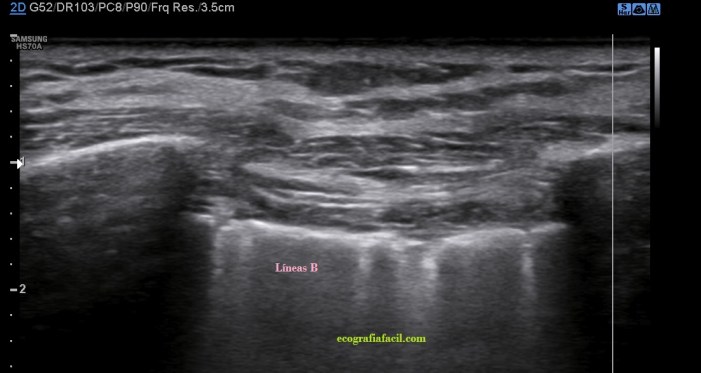

Si por el contrario, viésemos esta imagen…

Líneas B.Esta visualización del espacio intercostal indica Líneas B (flechas rosas), patología de diversa índole, normalmente, por la pérdida de la aireación normal en el contexto del síndrome intersticial y la presencia de tejido inflamatorio y/o líquido en esa región del pulmón que permite el paso de los trenes de ultrasonidos produciendo este tipo de imagen que es también otro artefacto, esta vez en cola de cometa.

Este artefacto aparece cuando el haz de ultrasonidos choca contra una interfase estrecha y muy ecogénica apareciendo detrás de esta interfase una serie de ecos lineales.

El aspecto de una línea B es lineal, perpendicular, hiperecogénica. Ojo, estas líneas pueden aparecer en «normalidad», pero cuando son únicas, cuando son 3 o más en un mismo espacio intercostal, deben saltarnos las alarmas, son una línea roja que debemos comunicar a la radióloga, para que eventualmente la paciente o el paciente se evaluado con otras técnicas.

En una zona donde hay Líneas B no puede haber Neumotórax.

Nota Importante: Las líneas A y B, además de aparecer en la pantalla tienen que cumplir una serie de requisitos para que sean consideradas como tales, como pueden ser en el caso de las líneas B, que aparezcan en un número por encima de 3 y que además esas líneas verticales lleguen hasta la profundidad de la pantalla.